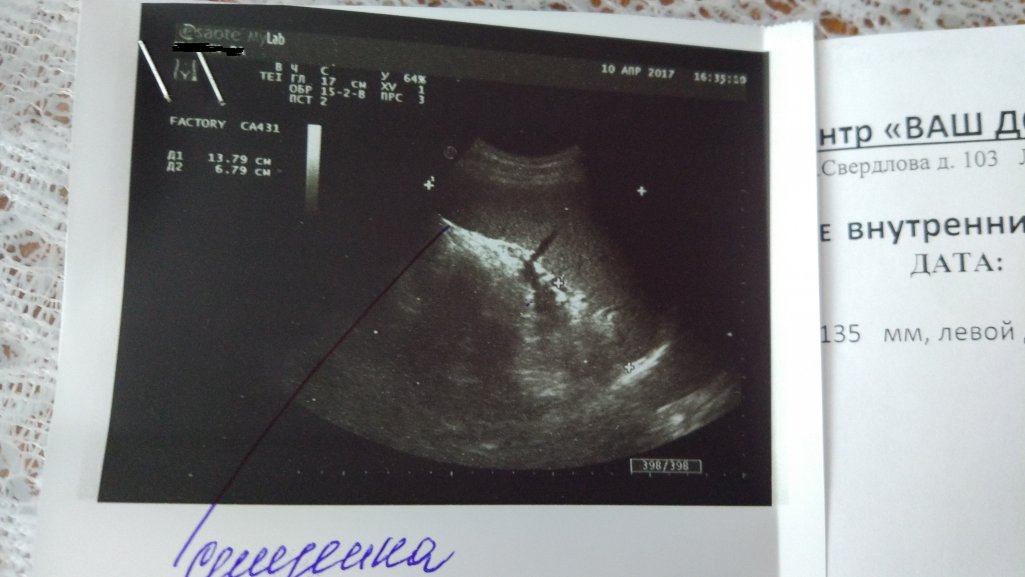

Добрый день друзья. Сделал сегодня более качественное платное узи, я когда сказал врачу которая делала узи, что у меня цирроз, она была сильно удивлена, и наверное в два раза дольше обычного смотрела мне печень своим аппаратом, говорит по печени вообще не скажешь, что цирроз. Так же как и в прошлом узи подтвердила, что увеличена селезенка и вена. Вы что скажете по узи? Так же сегодня сдал в инвитро оак и биохимию, завтра должны быть результаты, очень переживаю, ведь если аст и алт не упадут значит препараты не работают? Так же вычитал, что для поднятия тромбоцитов нужно пить настой крапивы, подскажите можно ли ее пить во время пвт и как заваривать и пить сие зелье?

По описанию печень и поджелудочная идеальные, что ставит под сомнение ЦП.Дмитрий27 писал(а):...когда сказал врачу которая делала узи, что у меня цирроз, она была сильно удивлена...

Но селезенка вступает в противоречие с ними: увеличена и ее вена - тоже.